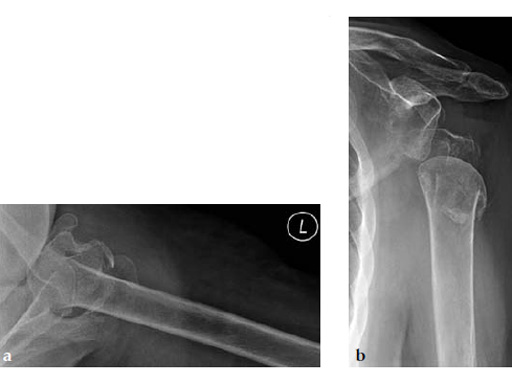

A 72-year-old woman suffered a four-part fracture of the left proximal humerus following a fall from a standing height. The patient underwent open reduction and internal fixation of the proximal humeral fracture.